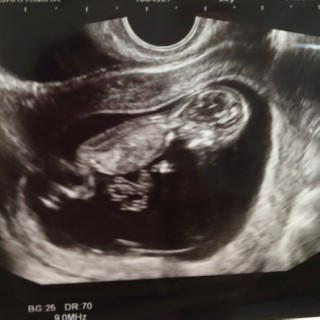

9wの時に切迫流産になりかけて不安でしたが…今はこんなに大きく元気に動いてました(*´∀`*)早く会いたいと毎日おもってます(*^^*)

やっと12w。へその緒もしっかり確認して、手足をばたつかせてて可愛かったです(^^)